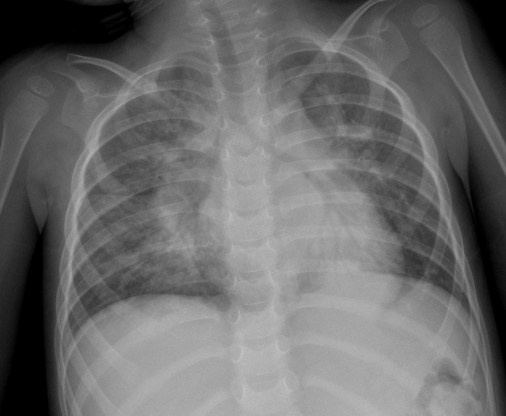

CASO: Pediátrico de más de 2 años tratado por porceso oncológico que ha comenzado con febricula y tos.

Hallazgos:

- Parénquimas pulmonares y silueta cardiomediatínica sin alteraciones significativas. No hay foco neumónico.

- Catéter reservorio subcutáneo con extremo distal en aurícula derecha.

- Resección de la porción anterior de la 6ª costilla. Suponemos que es ahí donde radicaba su proceso de base